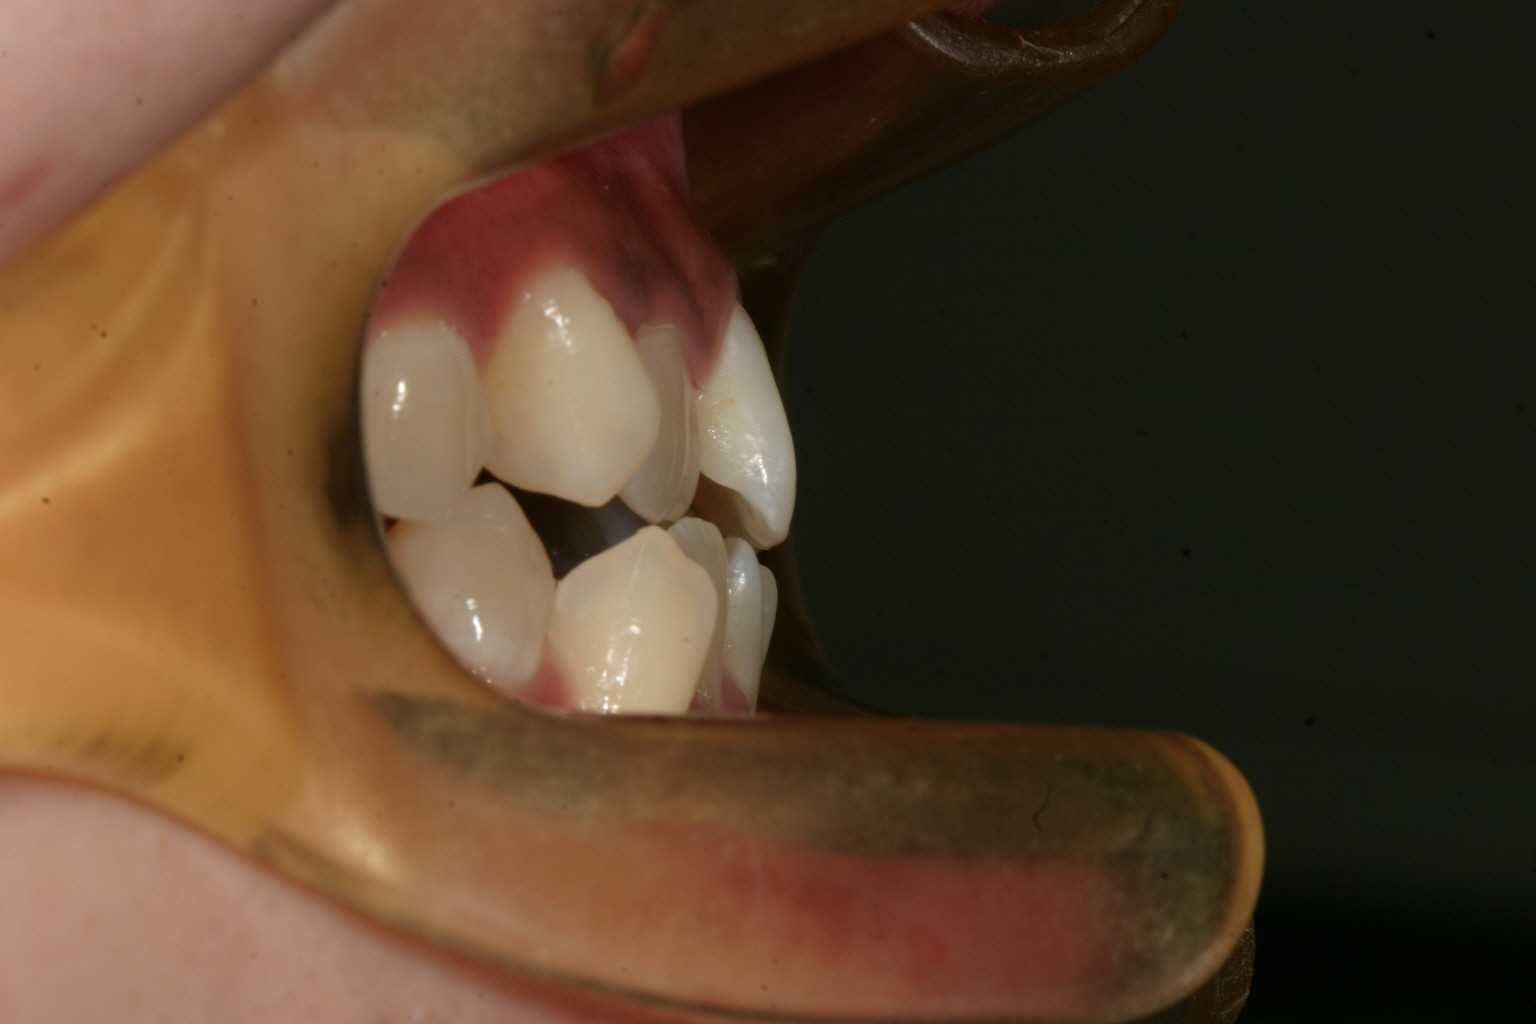

横から拝見しますと受け口っぽいですね~

上下の被蓋関係も良好です。